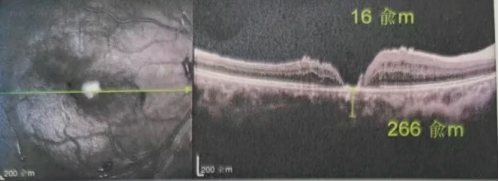

最讓吳爺爺難以置信的是:術(shù)后只需保持平躺24小時(shí)!第二天復(fù)查時(shí),眼底鏡及OCT檢查清晰顯示——那個(gè)折磨了他大半年的大裂孔,竟然閉合了!且吳爺爺?shù)挠已垡暳τ辛嗣黠@的改善,術(shù)后3天已經(jīng)可以看到 0.15。

李海波博士后表示:如果來得更早一些,他的視力還可以恢復(fù)得更好。但現(xiàn)在的治療結(jié)果對于經(jīng)歷過兩次失敗手術(shù)和漫長煎熬的他而言,已是奇跡。

李海波博士后指出:遠(yuǎn)周邊移植自體內(nèi)界膜覆蓋技術(shù)尤其適合那些反復(fù)多次手術(shù)裂孔仍未閉合,以及后極部沒有健康內(nèi)界膜可用的復(fù)雜病例。與傳統(tǒng)手術(shù)相比,該技術(shù)具有諸多獨(dú)特之處: